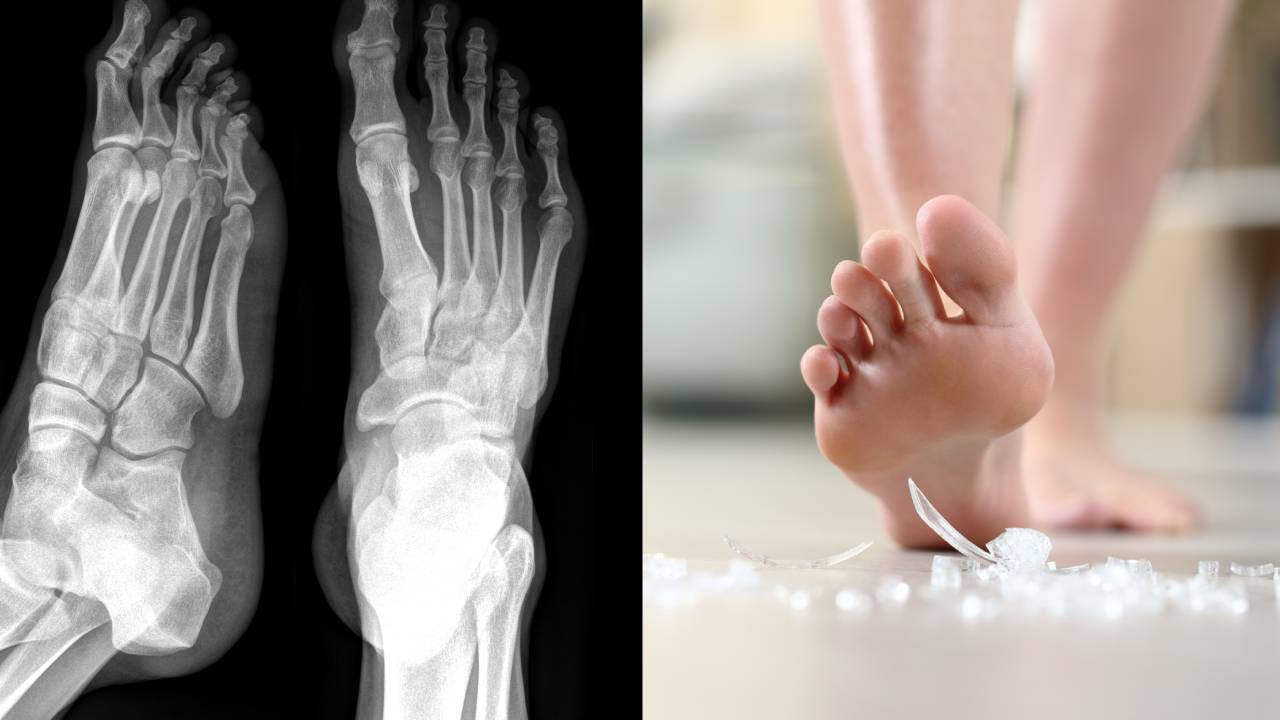

Arthritis So Bad That Walking Feels Like Stepping on Broken Glass

What if I told you that the pain, stiffness, and swelling in your feet caused by arthritis are actually tied to poor blood circulation, not just your joints?It sounds surprising, but it’s true.

See, your muscles and joints depend on healthy blood circulation to stay flexible and strong.

Without proper blood flow, your joints become stiff, your muscles weaken, and the pain intensifies.

As we age, our circulation slows down, and our feet—being furthest from the heart—are the first to suffer.

Without enough blood flow, our joints become rigid, and our muscles weaken, leading to that unbearable arthritis pain.

That’s why you might feel like your feet are “locked up” or stiff as if they’re stuck in place.